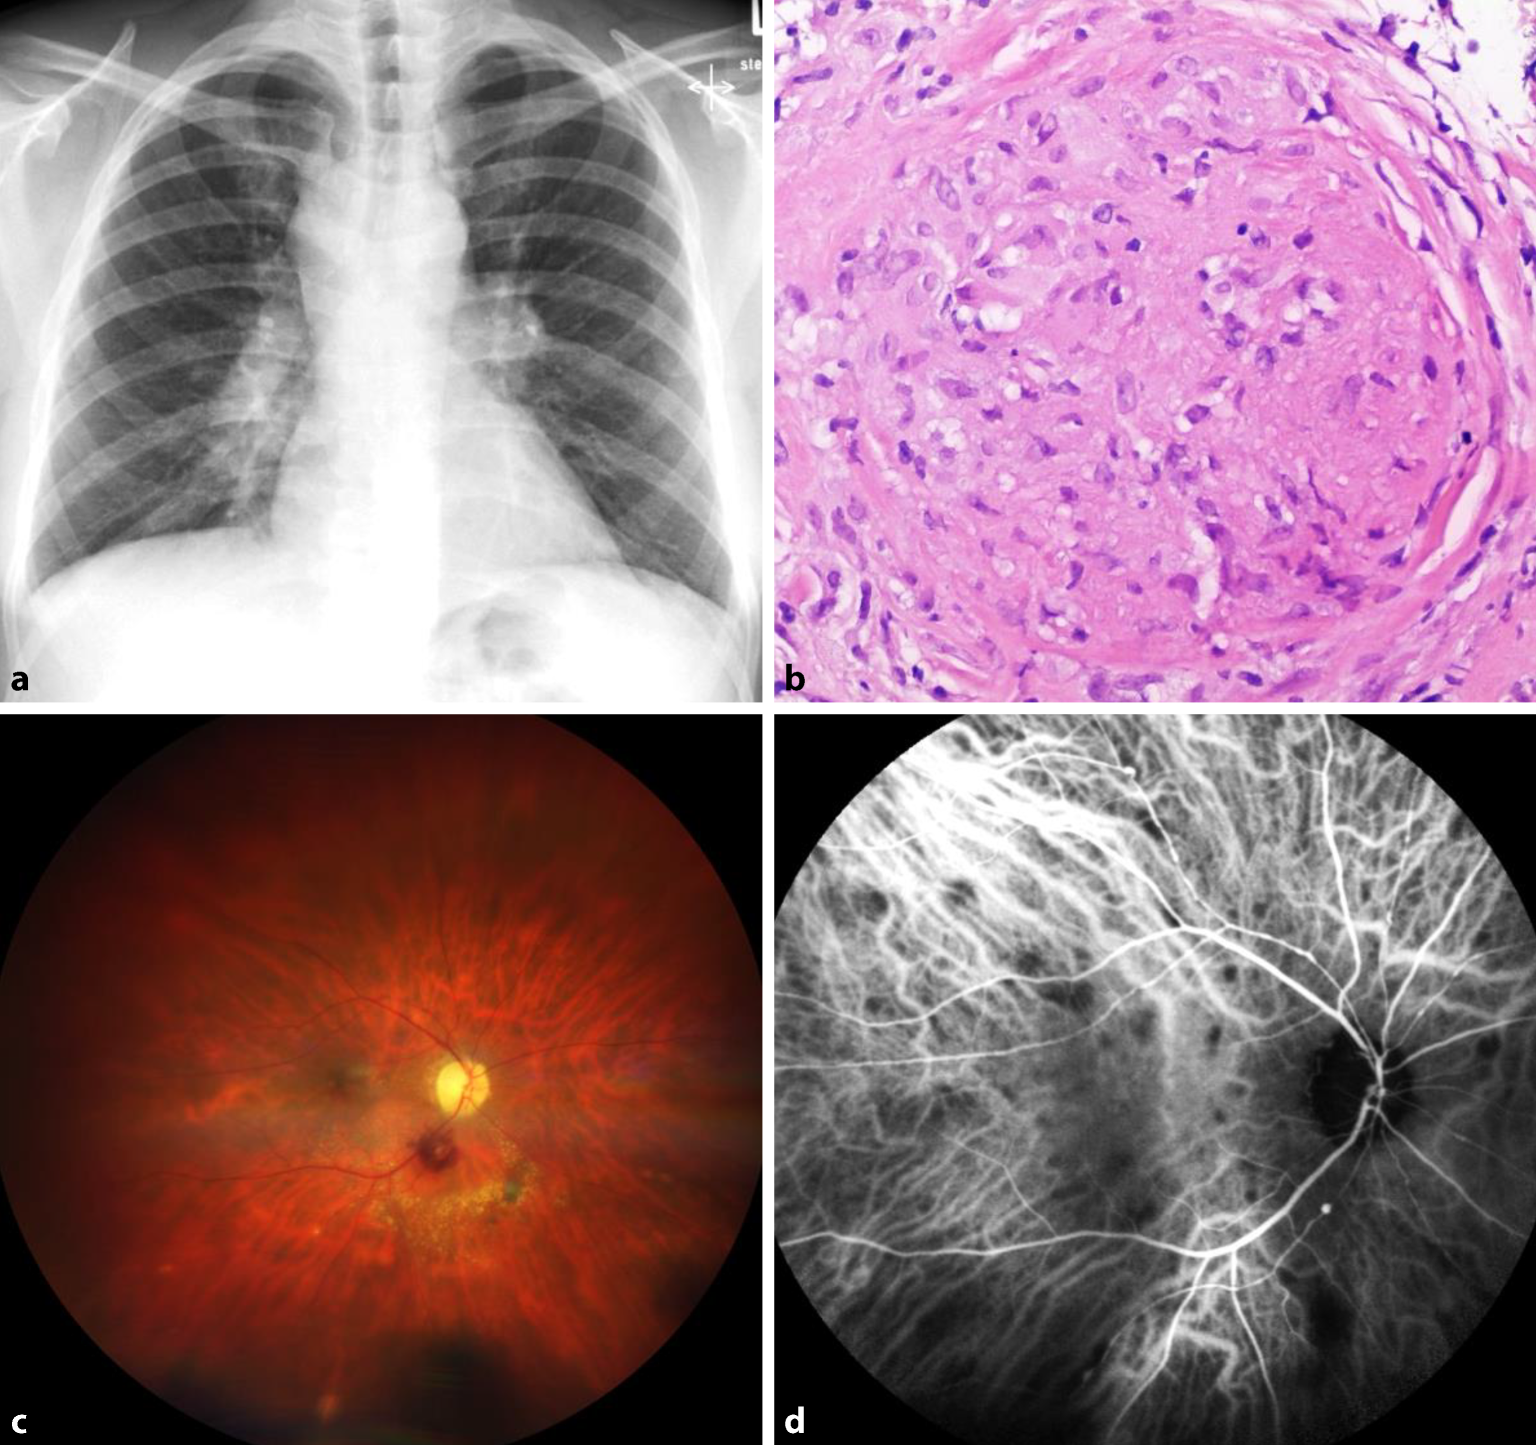

Abb. 5

Veränderungen bei Sarkoidose. a Röntgenaufnahme des Thorax bei bihilärer Lymphadenopathie. b Sarkoidosegranulom mit Schaumann-Körperchen aus dem Lymphknoten in HE(Hämatoxylin-Eosin)-Färbung. c Fundusfotografie bei okulärer Sarkoidose mit Aneurysma am unteren Gefäßbogen und choroidalen Granulomen. d Indocyaningrünangiographie mit hypofluoreszenten Läsionen in der Frühphase/mittleren Phase durch Minderperfusion der Choriokapillaris in Bereichen kleiner choroidaler Granulome

Die okuläre Sarkoidose ist in Deutschland eine der häufigsten systemischen Assoziationen der Uveitis und Vaskulitis der Retina [11]. Eine okuläre Beteiligung kann auch ohne eine systemische pulmonale Sarkoidose vorliegen. Die Kriterien des International Workshop on Ocular Sarcoidosis (IWOS) ermöglichen die Diagnosestellung durch eine Kombination von klinischen Befunden, Labordiagnostik sowie Bildgebung bihilärer Lymphadenopathie im Röntgen Thorax [12]. Ein klinisches Kriterium ist die charakteristische Phlebitis, die segmental auftritt. Bei ausgeprägtem Befund kommt es zum sog. „Kerzenwachsphänomen“ [13]. Außerdem zählen Makroaneurysmen zu den Diagnosekriterien (Abb. 5). Neben dem primär guten Ansprechen auf eine Steroidtherapie sind bei persistierender Inflammation bDMARDs zur Entzündungskontrolle indiziert.